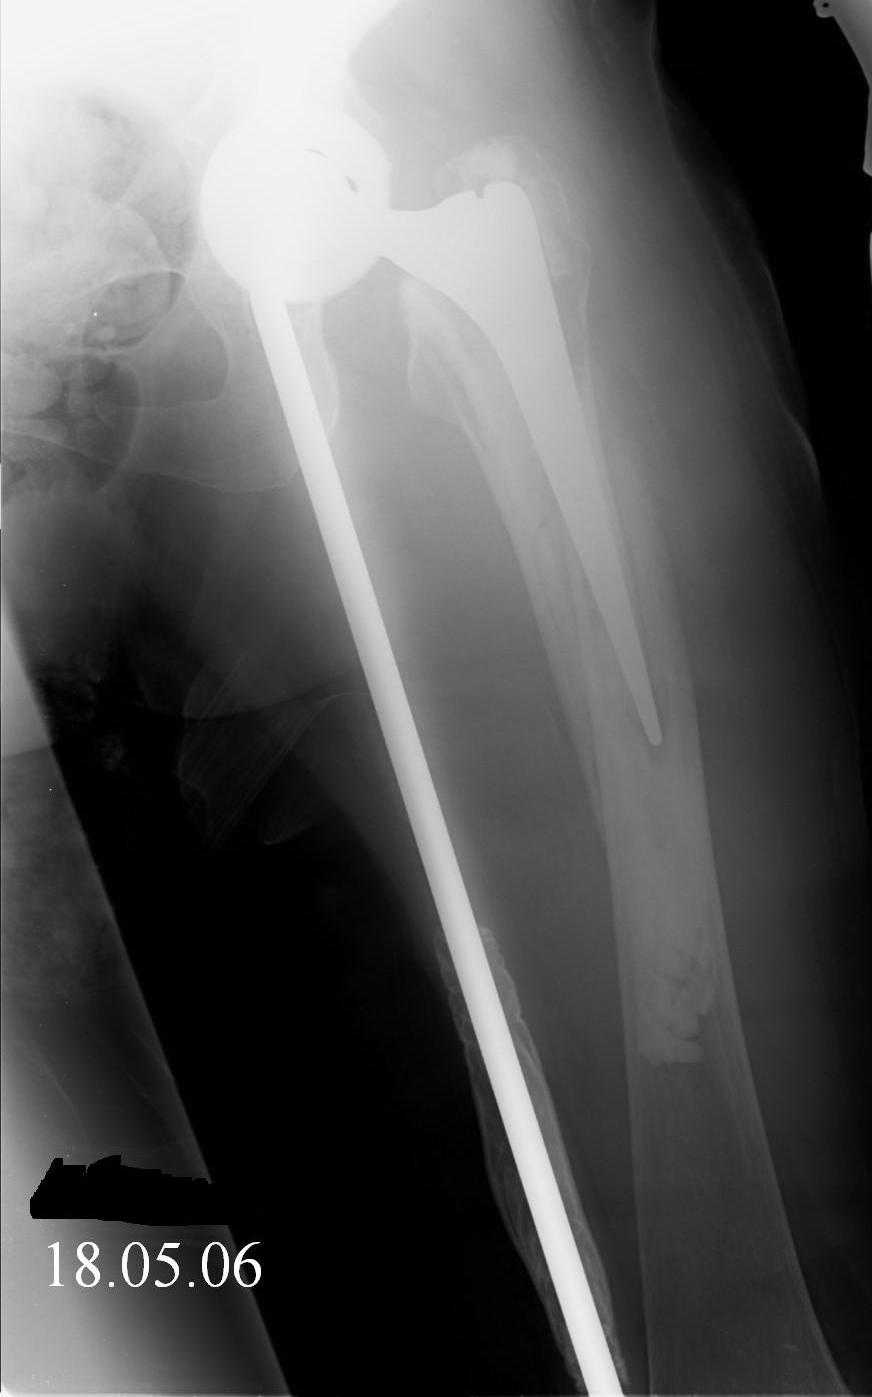

Female, rheumatoid, THA in 2003, car accident in 2006, failed plating. Nailing in Oct 2007. The nail is solid with hollow proximal part where the stem is docked. Last images are in 1 year after

nailing.

Спасибо за обсуждение. После нескольких дней тракции аппаратом сделали. Попытка закрытой репозиции не удалась из-за смещения по ширине, мешали фрагменты цемента. После их удаления репозиция получилась. Еще убрали немного цемента с ножки по латерльной стороне, чтобы обнажить 40-50 мм ее дистальной части, для плотной посадки гвоздя. Дальнейшее введение гвоздя было несложным. Протез показался нам стабильным в проксимальной части как латерально, так и медиально. Картинки в приложении.

THX for the discussion. After few days of traction by ex-fix the surgery was performed. An attempt of closed nailing was unsuccesful because of fragment translation, which was blocked by cement fragments. After removal of broken cement pieces reduction was reached "automagically". Also some cement from lateral part was removed by

chisel to expose distal 40-50 mm of the stem to allow tight fit of the nail. Further fixation by the nail was pretty easy and straightforward. Images attached. The stem looked stable in its proximal part both laterally and medially. Comments/critics are welcome.